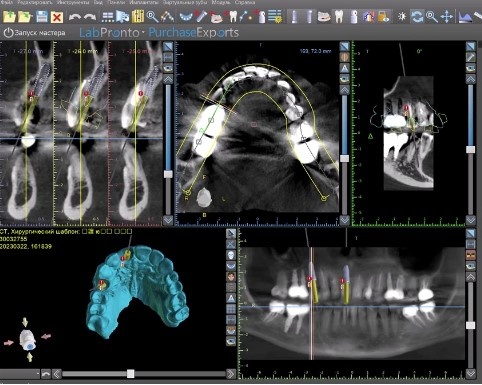

Сопоставление в специальной программе данных компьютерной томографии и цифрового скана зубов.

С учетом данных компьютерной томографии я отмоделировал и распечатал на 3D принтере: хирургический шаблон, который позволил установить имплантаты в наиболее правильной позиции с учетом всех анатомических особенностей строения челюсти и зубного ряда, а так же временные коронки.